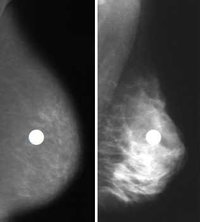

脂肪の割合が多い乳房のマンモグラフィー=写真左=と、脂肪が少ない乳房のマンモグラフィー=同右=を比べてください。左の脂肪性乳房では、中に描いた白いしこり(白丸、模擬病巣)のコントラストがはっきりして病巣が目立ちます。右は乳房全体が白く映し出される高濃度乳房で、白いしこりとのコントラストがはっきりしないため病巣を探し出すのが難しそうだということが分かると思います。このように、その人の乳房の特徴により病気の見つけやすさが違ってくるのがマンモグラフィーの特徴です。